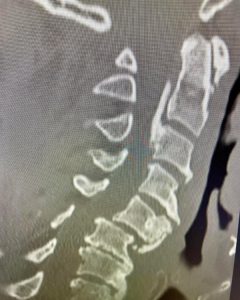

Here is an example of another cervical spine case: MRI and CT scans show a 54 year-old male who had a cervical fracture dislocation at C5-6 after diving forward into shallow water and striking his head. He was fortunate not to be paralyzed. The patient also had chronic conditions in his cervical spine that put him at even higher risk. He had severe cervical stenosis, or narrowing of the spinal canal. He also had a somewhat rare condition called OPLL or ossification of the posterior longitudinal ligament.